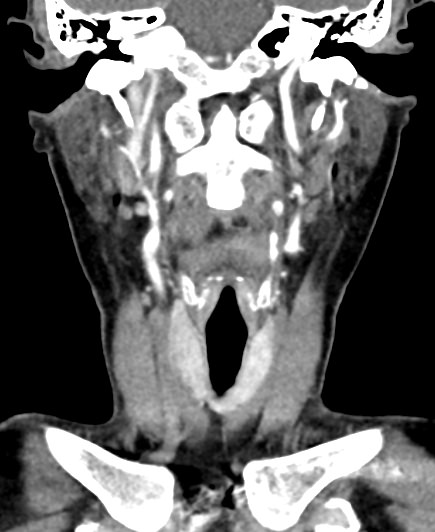

Мультиспиральная компьютерная томография – это высокоинформативный лучевой метод диагностики различной патологии мягких тканей шеи, включая воспалительные заболевания, травматические повреждения и опухолевые процессы. КТ позволяет оценить состояние щитовидной железы, паращитовидных желез, гортани, верхней части пищевода, магистральных сосудов шеи, шейных лимфоузлов и окружающих мягких тканей.

Метод КТ основан на применении рентгеновского излучения. Однако в отличие от обычного рентгена, при котором снимки производятся в одной плоскости, при КТ излучатель рентгеновских лучей постоянно двигается вокруг объекта исследования, проводя сканирование в различных плоскостях, а затем трансформируя полученные данные в цифровые трехмерные изображения. Это дает возможность визуализировать органы и ткани в мельчайших подробностях, а с помощью объемных 3D-реконструкций наглядно оценить пространственное расположение органов и патологических образований.

Рентгеновские лучи лучше всего поглощаются плотными структурами, такими как костная ткань. Поэтому кости хорошо видны на снимках КТ. Это делает компьютерную томографию незаменимой при необходимости обследования, в частности, костного скелета гортани. Однако для улучшения визуализации мягких тканей требуется введение специального контрастного препарата, поэтому КТ мягких тканей шеи проводится с контрастным усилением.

Для контрастирования используется йодсодержащее контрастное вещество, которое в составе рентгеноконтрастного препарата вводится в вену пациенту непосредственно во время исследования. Благодаря способности контраста поглощать рентгеновские лучи на снимках КТ хорошо контрастируются кровеносные сосуды и опухолевые образования, имеющие, как правило, развитую сосудистую сеть. Методика внутривенного болюсного контрастирования помогает обнаружить воспалительные изменения, отличить доброкачественные опухоли от злокачественных, выявить поражение лимфатических узлов и степень прорастания опухоли в магистральные сосуды и окружающие ткани.